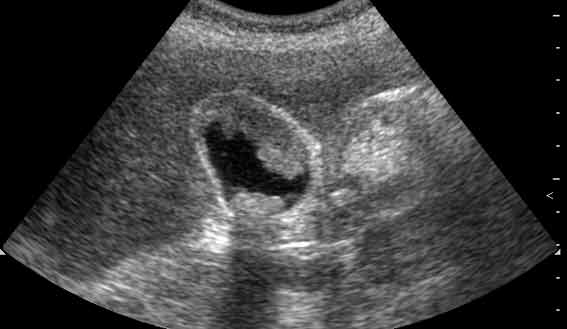

Опухоль передней стенки и конкременты желчного пузыря.

Tags: Tumor the anterior wall and of the gallbladder, stones.